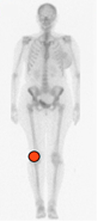

Fig 67. Distribución de la artropatía por hemofilia.

Principal compromiso de la rodilla.